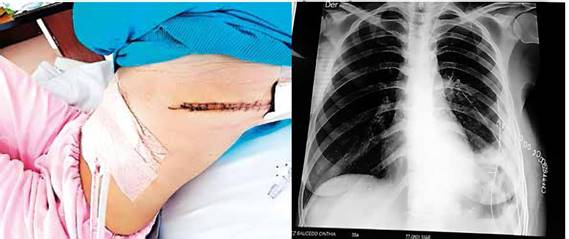

Durante PO inmediato y mediato no hubo eventualidades; pasó a sala de cirugía posterior a estar 3 días en UTI. Se mantuvo manejo endovenoso de medicación además de controles laboratoriales con gran mejoría; se inicia dieta al 5to día PO, además de RX de tórax de control sin hallazgos patológicos. Se efectuó interconsulta con fisioterapia quien inicia terapia ventilatoria tanto activa como pasiva. Es dada de alta 7mo día en buenas condiciones (FIGURA 4).

FUENTE: PROPIA EXPEDIENTE CLINICO

FIGURA 4: Evolución post operatoria